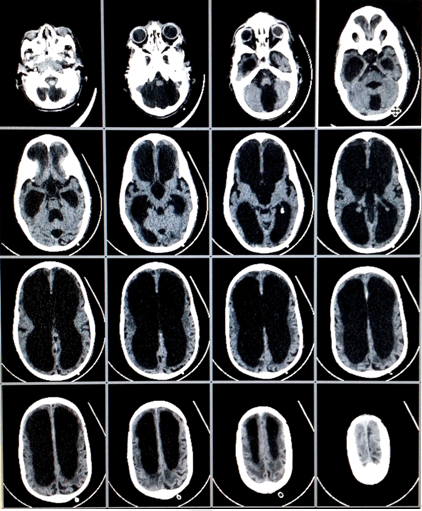

A five-year-old boy was presented to the emergency department with his parents with a history of falling from height. They lived in a rural area near Alexandria city. The father works as a farmer and the mother is a housewife, both of them were illiterate. The child was born term by normal labor. There was a history of an increased head size at birth, but the parents neglected this observation and they did not seek any medical advice although the head increased in size gradually over the time. Once the child was examined, a significant large head size of the child was noticed, which was not the complaint of the parents. The child was underweight (11 kg) and his height was less normal in his age group (80 cm). At the beginning the child was not alert but after a short while he gained his consciousness. There were signs of mental retardation, drowsiness, impaired speech, short attention span and impairment in physical coordination. The parents reported problems in his learning abilities. Upon examination of the head, its circumference was 66 cm. The scalp skin was shiny with apparent veins. Eye examination showed (setting sun sign). Computed tomography (CT) scan of brain revealed enlarged frontal and posterior horns of the lateral ventricles and enlarged third and fourth ventricles. Such bilateral huge ventriculomegaly is accompanied by severe brain parenchymal loss as illustrated (Figure 1) and (Figure 2). It was noticed also that the enlargement of the ventricles is out of proportion with sulcal atrophy, i.e., relative normal sulcal size, which is an indication of normal intracranial pressure. The images of the patient's brain were examined concerning the trauma that the child had after falling from height. The CT scan did not show any problem that happened due to the fall or any kind of hemorrhage. The parents were assured that the trauma did not cause any problem and were informed about such neglected case of hydrocephalus and that the child will most probably have a normal life span. They were told, however, that there is no cure for such condition and the patient was booked for an appointment at the rehabilitation center which will help the child to cope with the activities of the daily living and improve his cognitive function. The child was discharged without any surgical intervention after a full system examination which cleared the child. Moreover, we told the parents that they must attend a follow-up visit every six months with the neurology department in the hospital so that the child's symptoms are monitored. | ||||||